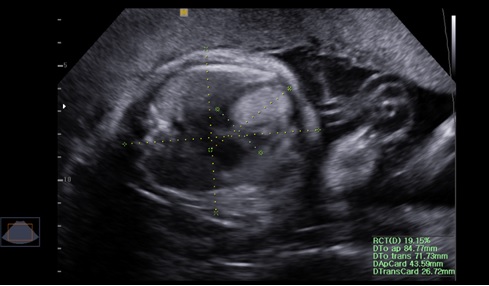

Esclerosis tuberosa: diagnóstico prenatal, tratamiento y seguimiento de un año. Reporte de caso

Yolima Alfaro, Luis Fernando Molineros, Gabriel Del Castillo, Melissa Charria Caicedo, David Farah Borrero